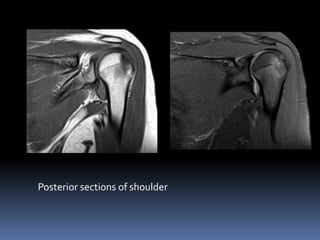

Posterior sections of shoulder